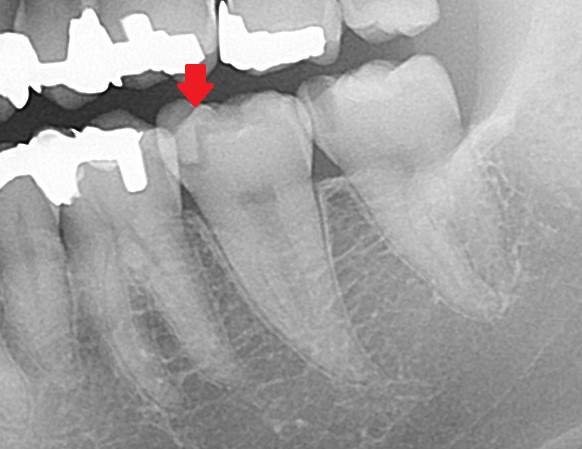

では、小さい虫歯はどうでしょうか?

奥歯の虫歯なのですが、どこにあるかわかりますか?

正解は・・・

こちらが全て虫歯です。

よく見れば大きい「C3」の虫歯もありますが、小さい虫歯だらけの状態です。

虫歯は歯と歯の間から虫歯になっているために、患者さん自身では気づいていませんでした。

ここで「C1~C2」とあります。虫歯はが大きくなると判別つきやすいのですが、小さいものは正確に範囲が分からないことが多いです。

ですのでレントゲンからでは、虫歯があるのは分かりますが「C2まで進行しているかなぁ?」と推測することまでしか出来ません。

実際に治療をすると「C2」だったと後で分かります。

正直、虫歯は分かりにくい場合も多くある。ということは、歯医者の先生によって見逃される場合も多くあるともいえます。